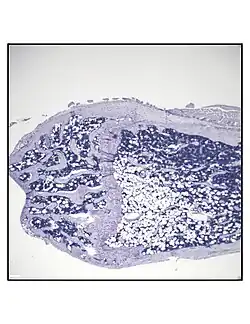

Representative distal femur histologic section of a 16-week-old healthy C57BL/6 mouse demonstrating a typical quantity of marrow adipocytes. -